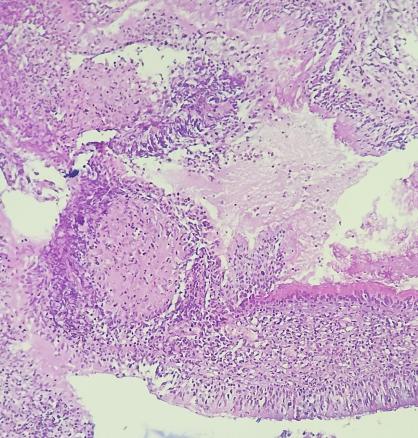

Une patiente âgée de 40 ans est admise à l’hôpital pour exploration d’adénopathies cervicales. L’interrogatoire révèle une obstruction nasale chronique accompagnée d’une rhinorrhée. L’endoscopie met en évidence une rhinite croûteuse avec un bombement du cavum (fig. 1). La tomodensitométrie montre un cavum pseudotumoral (fig. 2, 3 et 4). L’histologie objective un processus granulomateux tuberculoïde (fig. 5). Le GeneXpert sur fragment de biopsie, l’intradermoréaction à la tuberculine et la recherche de bacille de Koch dans les crachats sont négatifs.

La calcémie, la protéine C-réactive (CRP), l’angiotensine convertase et le bilan immunologique sont normaux. La confrontation des données cliniques, radiologiques, histologiques et biologiques retient le diagnostic de sarcoïdose. L’évolution a été favorable sous corticothérapie systémique.